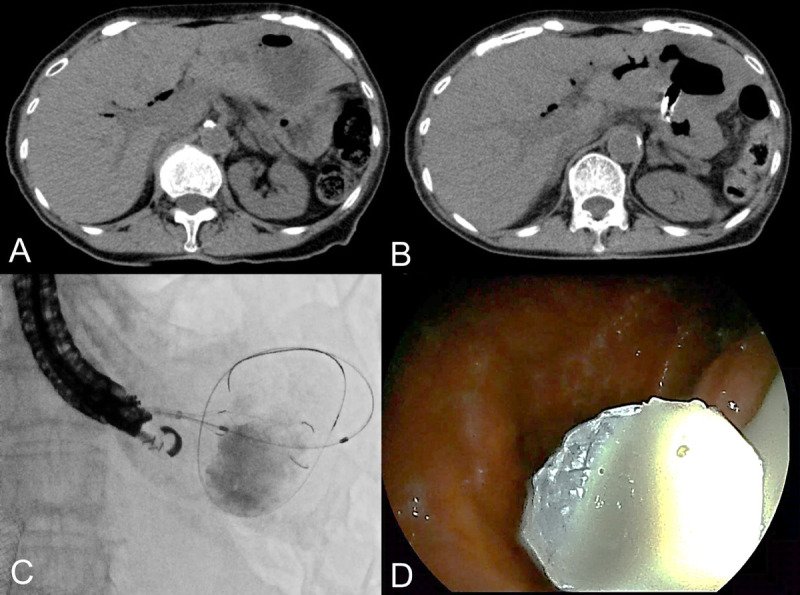

Background and objectives: Recent technological advances in interventional EUS have improved EUS-guided drainage/anastomosis (EUS-D/A), yet challenges remain. This study evaluated the safety and feasibility of a square flare fully covered self-expandable metallic stent (SF-FCSEMS) with anti-migration properties for EUS-D/A.

Methods: This retrospective cohort study was performed at 2 academic centers and analyzed patients who underwent SF-FCSEMS placement for EUS-D/A from April 2015 to November 2022. We have used an SF-FCSEMS that has a square flare at both ends that is 4 mm larger in diameter than the stent body, providing an anti-migration effect.

Results: Thirty-six patients (median age: 74 years), 41.6% male, were included. Malignancies accounted for 83.3%. Among the EUS-D/A procedure types, EUS-abscess drainage was performed in 52.8%, EUS-guided gallbladder drainage in 30.6%, and EUS-guided abscess drainage in 16.7%. The technical success rate was 97.2%, and the clinical success rate was 97.1%. The median procedure time was 36 minutes, with puncture tract dilation conducted in all cases. Adverse events occurred in 11.1%; recurrent symptoms were observed in 11.8%, with no migration. SF-FCSEMS removal was performed in 26.5% of patients during the follow-up period, with a median duration of 154 days. The total cost of deploying SF-FCSEMS was approximately 40% less than that of using lumen apposing metal stent.

Conclusions: EUS-D/A with an SF-FCSEMS, which has anti-migration properties, not only was effective and feasible in the present study but also demonstrated a cost advantage.